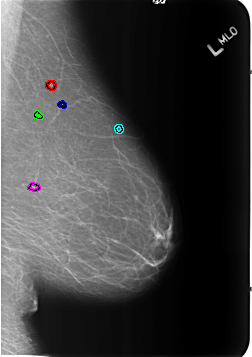

B_3188_1.LEFT_MLO

FILE: B_3188_1.LEFT_MLO.OVERLAY

TOTAL_ABNORMALITIES 5

ABNORMALITY 1

LESION_TYPE MASS SHAPE LYMPH_NODE MARGINS CIRCUMSCRIBED

ASSESSMENT 2

SUBTLETY 4

PATHOLOGY BENIGN_WITHOUT_CALLBACK

ABNORMALITY 2

ABNORMALITY 3

ABNORMALITY 4

ABNORMALITY 5